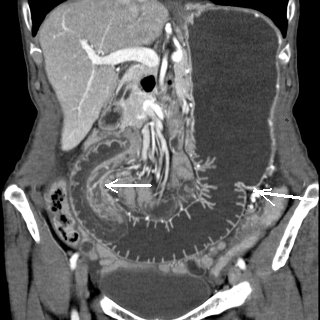

La CT scanner coronale

y avait le role importante dans diagnostic des

occlusion intestinale aigue :Y avait il de occlusion ? , la degree de occlusion ,

la situation de obstacle , la cause et les complications .

Aspect radiologique TDM de occclusion de l'intestin

grele est : |

La vue coronale

de TDM montrant la cause de l'invagination : Lipome

du grele de grand diametre